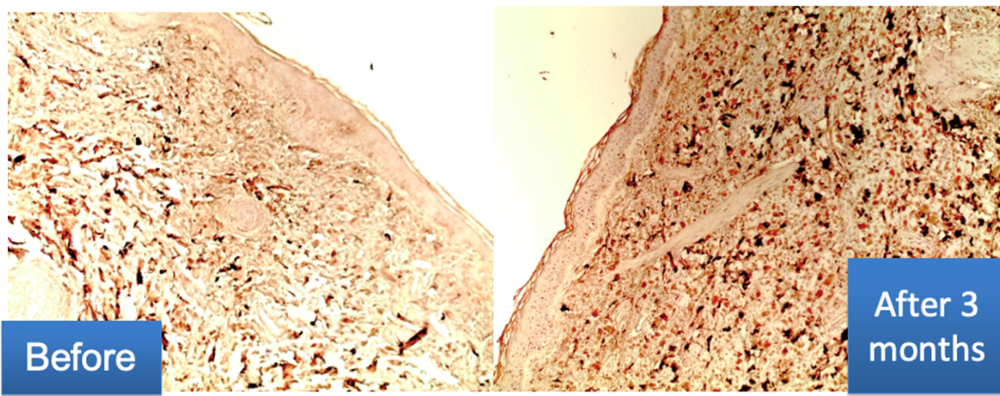

Examen immunohistochimique :

- La teneur en collagène III dans le derme est notablement augmentée.

- La formation de fibres orientées longitudinalement